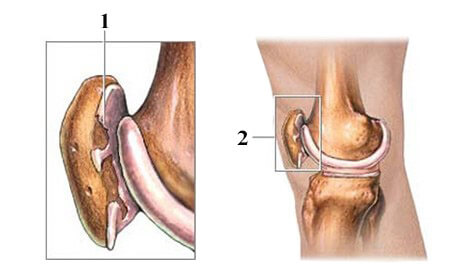

Хвороба Кеніга (розсікаючий остеохондрит колінного суглоба) – досить рідкісне захворювання, при якому розвивається обмежений остеонекроз ділянки субхондральної кістки, внаслідок чого відбувається дегенерація та відділення хрящової тканини в ділянці некрозу з подальшим зміщенням фрагмента